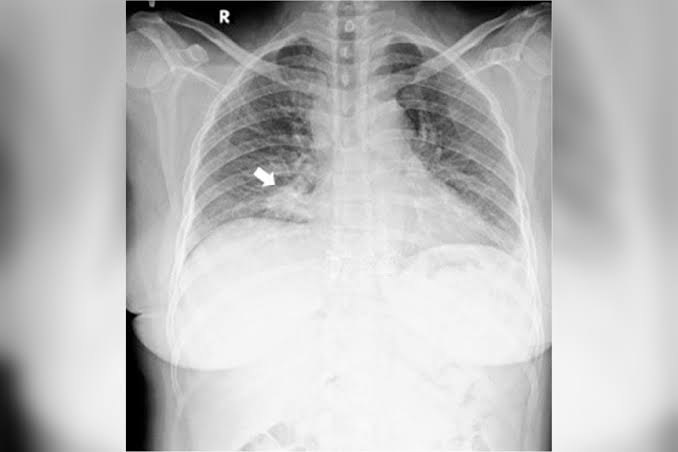

A partir da realização de exames, os médicos notaram uma grande lesão abaixo da retina do olho direito e a mesma lesão, só que menor, no olho esquerdo. Foi então que a equipe colocou a mulher para fazer uma radiografia, que encontrou o nódulo na zona inferior do pulmão direito.

A partir desses exames, outros foram feitos e mais tumores foram encontrados em outros órgãos. A mulher, que não teve seu nome revelado, foi diagnosticada com carcinoma de pulmão e com metástase de coróide (membrana que envolve o olho) em ambos os olhos.